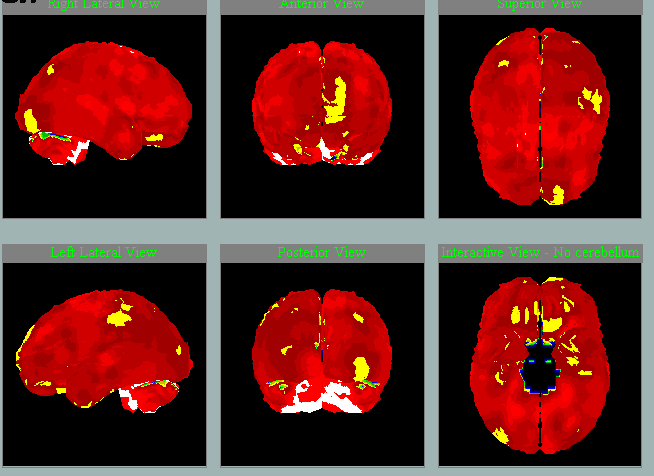

V letech je možné vidět přibývání hypoperfúze a tedy progresi:

2011

2014

2020